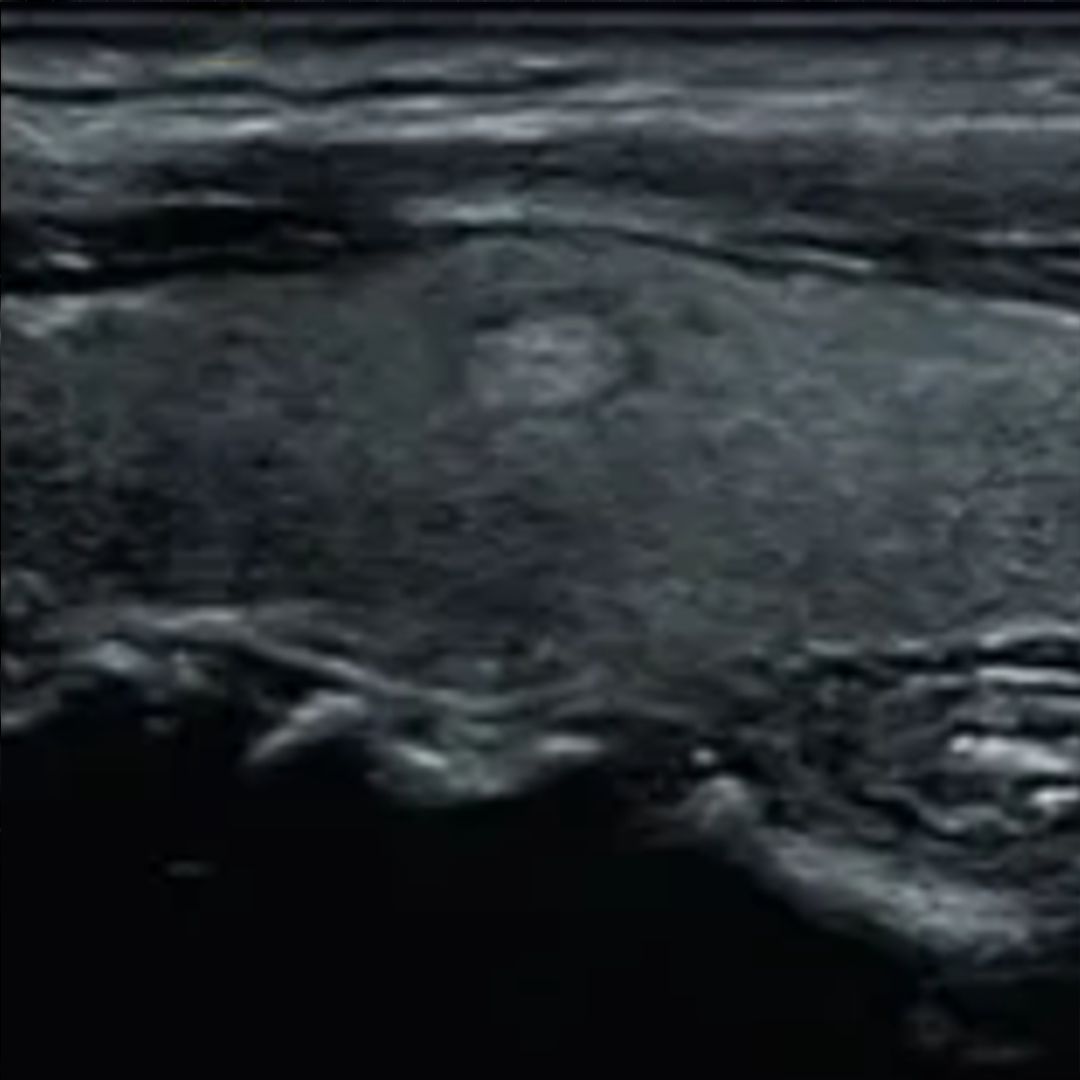

04、看囊实性

依据结节内部成分的不同可以将结节分为:

1. 囊性结节:内部成分为液体;

2. 实性结节:内部成分为固体;

3. 囊实性结节:内部成分既有液体,也有固体。

恶变的几率依次为:实性结节>囊实性结节>单个的囊性结节>多发的囊性结节。

甲状腺囊性,囊实性和实性结节超声图像